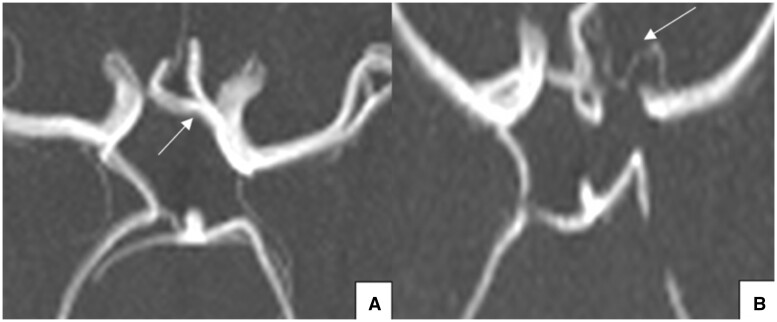

Objectives: This article seeks to determine the prevalence of a complete circle of Willis (CoW) and its common morphological variations in a south Trinidad population, while also investigating the influence of gender, age, and ethnicity on CoW morphology.

Methods: A prospective, descriptive, cross-sectional study was done on the magnetic resonance images for consecutive patients who had a brain MRI/magnetic resonance angiography at a tertiary health institution in south Trinidad between October 2019 and September 2020. Patients with significant cerebrovascular disease and/or a history of prior neurosurgical intervention were excluded.

Results: A complete CoW was seen in 24.3%, with more complete circles observed in younger participants (≤45 years) and Afro-Trinidadians. No gender predilection for a complete CoW was demonstrated. The most common variations in the anterior and posterior parts of the circle were a hypoplastic anterior communicating artery (8.6%, n = 13) and bilateral aplastic posterior communicating arteries (18.4%, n = 28), respectively.

Conclusions: Significant variations exist in the CoW of a south Trinidad population with a frequency of complete in 24.3%, and more complete circles in younger patients and Afro-Trinidadians. Gender did not influence CoW morphology.

Advances in knowledge: Structural abnormalities in the CoW may be linked to future incidence of cerebrovascular diseases and should therefore be communicated to the referring physician in the written radiology report. Knowledge of variant anatomy and its frequency for a particular populations is also required by neurosurgeons and neuro-interventional radiologists to help with preprocedural planning and to minimize complications.